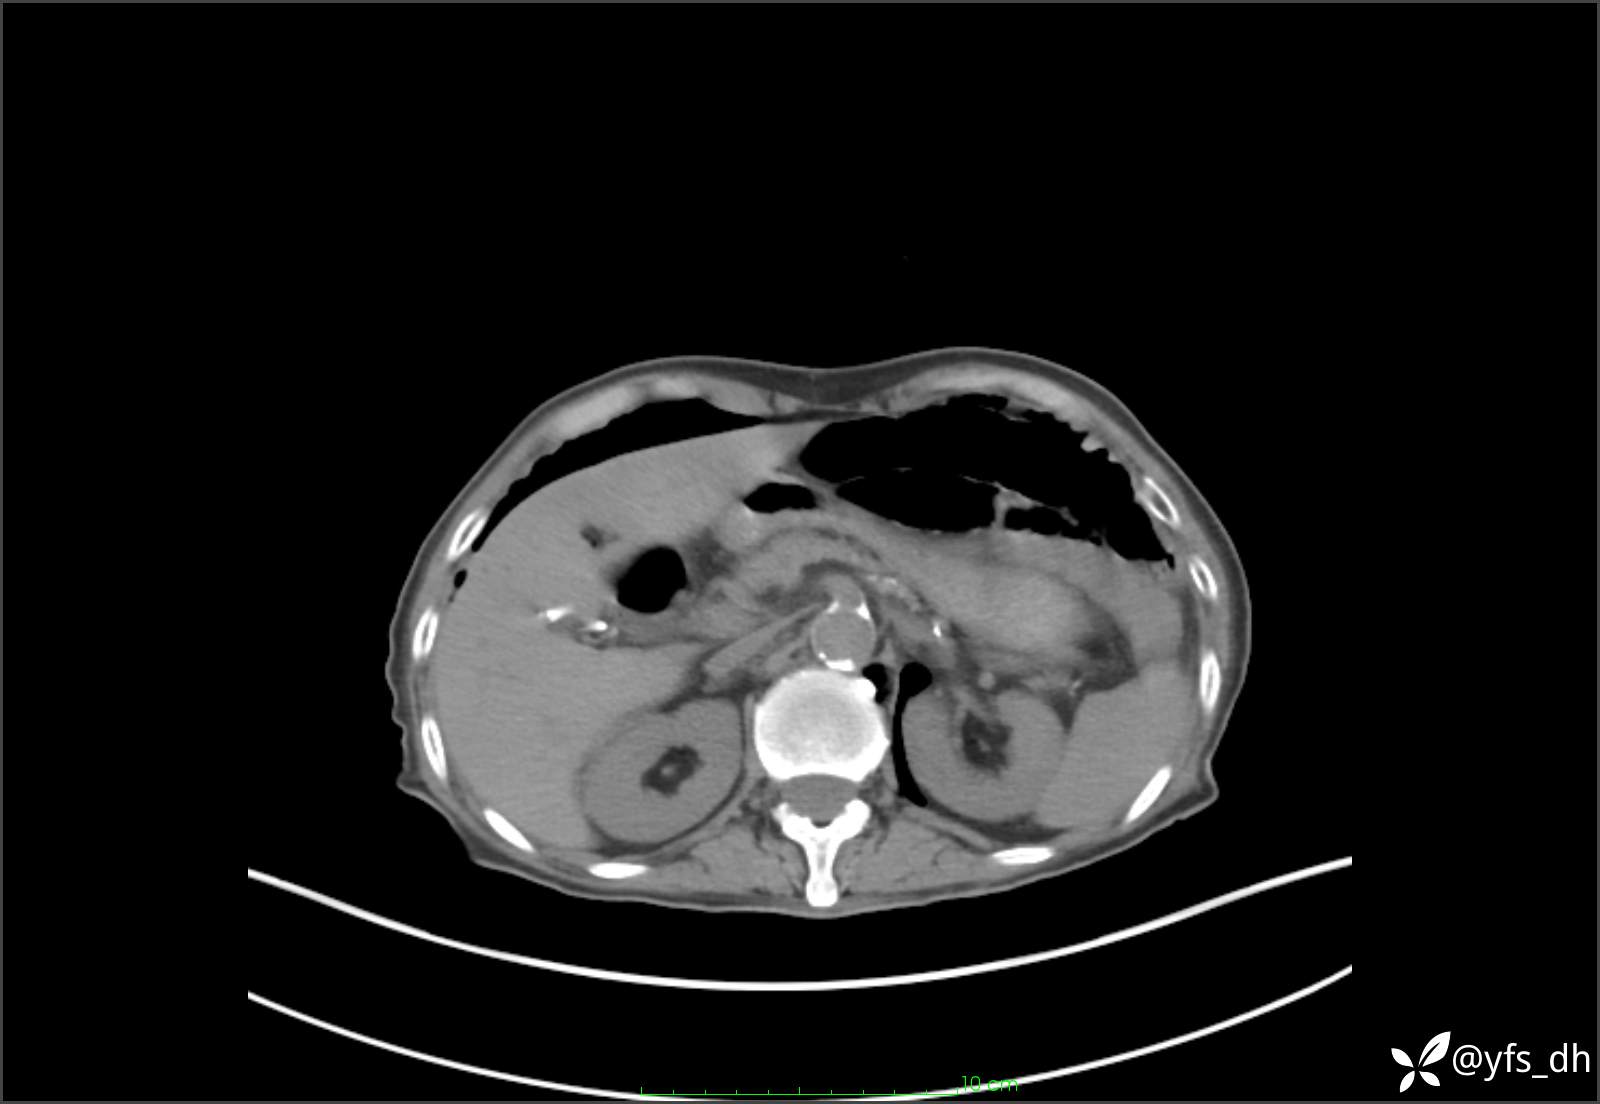

1.简要病史:患者4天前突发上腹部疼痛不适,但可以忍受。3小时前饭后突然加重,不能忍受后就诊。

2.简要手术记录:术中见腹盆腔大量肠液及粪便,乙状结肠中下段见一约3cm的破口。